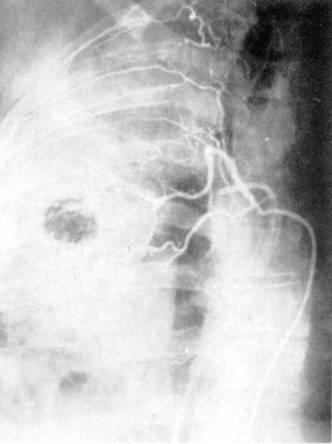

Рис. 6. Ангиопульмонография.

а — артериальная фаза; б — капиллярная

фаза; в — венозная фаза.

Рис. 7.

Селективная ангиография бронхиальных артерий.

анализе ангиопульмонограмм обращают внимание на пофазовое продвижение контрастного вещества по

различным регионам легкого: легочной артерии, капиллярного русла, венозной

системы малого круга кровообращения (рис. 6).

По комбинации ангиографических признаков представляется

возможным охарактеризовать вид и распространенность патологического процесса

(при двухпроекционной сериографии — посегментарно) в легком, при этом обращается внимание

на наличие деформации сосудов, смещение, контуры, разреженность сосудистого рисунка

(рарефикацию), степень развития сосудов отдельных

сегментов, долей, легкого, характер расположения камер сердца, ротацию сердца и

др.

Сериография, проводимая, как правило, в

переднезадней проекции, может быть дополнена рентгенограммами в боковой или

косой проекциях в зависимости от задач исследования (рис. 7).